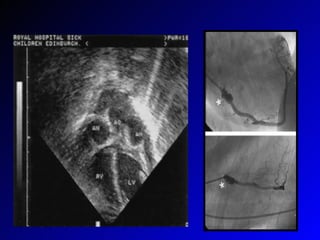

KH- Lab. Bulguları Hemogramda---Lökositoz, anemi, trombositoz KCFT’de bozulma Üretrite bağlı steril piüri(%25) CRP, ESR artar ANA, Anti-DNA, RF:- Endotel hücre antijenlerine, kardiyak miyozine karşı antikor+ EKG:PR uzaması, ventriküler aritmi, ST-T değ.  EKO:Ventriküler-Valvüler disfonksiyon, koroner arter anevrizması, perikardiyal eff.

İzlem-I Tanı sırasında ECHO Hastalığın 14. Gününde ECHO Başlangıçtan 6-8 hafta sonra ECHO Anevrizma + ise---akut fazda 48 saatte bir ECHO( büyüme?, tromboz?) ECHO’da anevrizma + ise ASA devam 6-12 ayda bir ECHO

KH- Lab. BulgularıHemogramda---Lökositoz, anemi, trombositoz KCFT’de bozulma Üretrite bağlı steril piüri(%25) CRP, ESR artar ANA, Anti-DNA, RF:- Endotel hücre antijenlerine, kardiyak miyozine karşı antikor+ EKG:PR uzaması, ventriküler aritmi, ST-T değ. EKO:Ventriküler-Valvüler disfonksiyon, koroner arter anevrizması, perikardiyal eff.

İzlem-I Tanı sırasındaECHO Hastalığın 14. Gününde ECHO Başlangıçtan 6-8 hafta sonra ECHO Anevrizma + ise---akut fazda 48 saatte bir ECHO( büyüme?, tromboz?) ECHO’da anevrizma + ise ASA devam 6-12 ayda bir ECHO